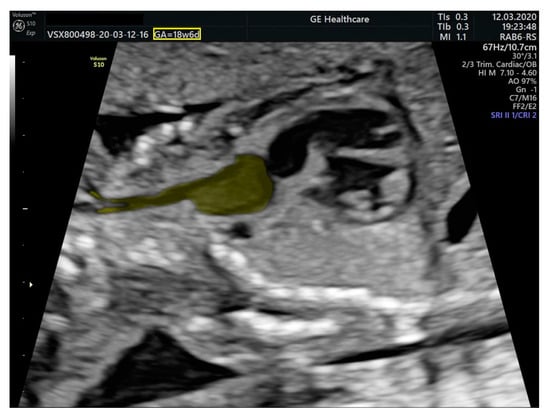

- an isolated aortic arch anomaly (supposedly aneurysmal dilation from which the left common carotid artery emerges) and coarctation of the aorta with the anterograde flow;

- ventricular septal defect, coarctation of the aorta, and a vascular formation located superior from the aortic arch with the appearance of an arteriovenous fistula;

- aneurysmal dilation located above the pulmonary trunk bifurcation and a dilated left common carotid artery with a retrograde flow;